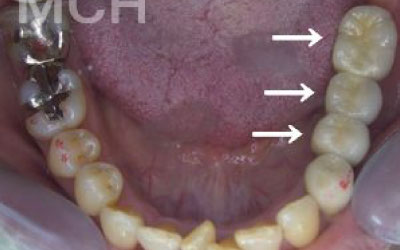

「お口の状態や噛み合わせによって異なるため一概には言えませんが、一般的には奥歯が適しています。

特に、一番奥の歯とその隣の二番目の奥歯が重要です。

噛み合わせの力の60%以上がこの2本の奥歯で支えられているため、ここをしっかりとインプラントで治療するのが理想的です。